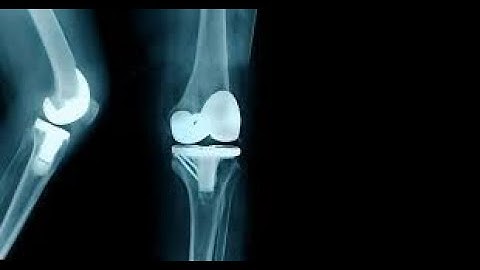

Arthroplasty with prosthetic replacement CPT code - simplify medical coding